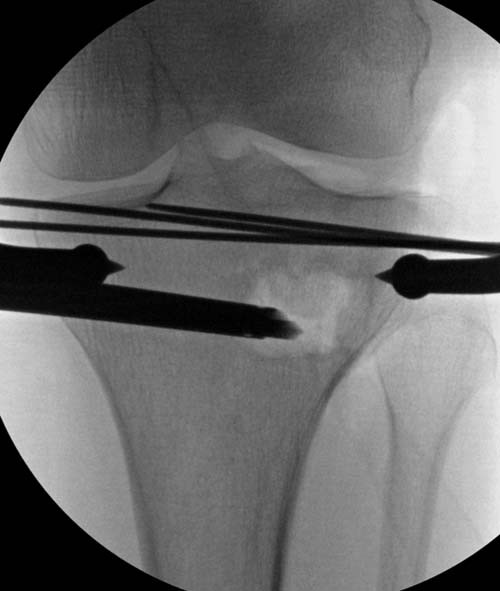

Для лечения некоторых видов центральной импрессии (Schatzker III) можно применить методику Balloon tibioplasty, которая позволяет приподнять сустав без дополнительных доступов. Для информации здесь недавний пример, дефект заполнен жидкой формой композитного материала PRO-DENSE: http://www.wmt.com/prodense/product_overview.asp